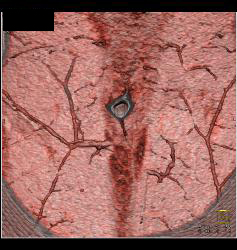

DIEP Flap Planning in 3D